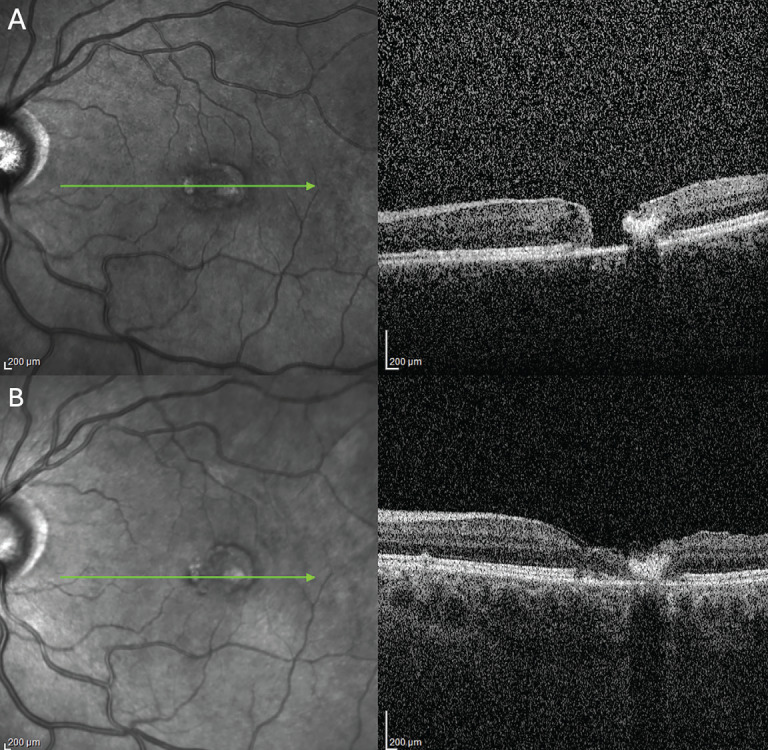

Objectives: To evaluate the long-term progression of macular telangiectasia type 2 (MacTel) using a standardized classification system and to assess the incidence, progression, and management strategies of complications such as macular neovascularization (MNV) and macular hole (MH).

Materials and methods: This retrospective study analyzed the medical records of patients diagnosed with MacTel at a tertiary referral center in Türkiye from January 2004 to February 2025. Patients with a minimum follow-up of 3 years and no confounding macular pathologies were included. Data collection included best corrected visual acuity (BCVA), multimodal imaging (optical coherence tomography [OCT], fundus autofluorescence, fluorescein angiography), and demographic variables. Disease severity was classified using the MacTel Classification System developed by Chew et al. Longitudinal changes in BCVA and OCT parameters were statistically analyzed.

Results: A total of 184 eyes from 94 patients (mean age: 63.89±9.98 years; mean follow-up: 79.27±50.69 months) were included. A significant decline in BCVA was observed (p<0.001). MNV was present in 29 eyes (15.8%), with 18 receiving intravitreal anti-vascular endothelial growth factor (anti-VEGF) therapy (mean injections: 5.89±3.72). While posttreatment BCVA showed improvement (p<0.001), long-term visual outcomes were not significantly different from baseline (p=0.213). MH formation occurred in 8 eyes (4.3%), with 6 undergoing successful surgical closure. Structural retinal changes, including ellipsoid zone disruption and pigmentation, significantly progressed over time (p<0.001).

Conclusion: MacTel demonstrates a progressive decline in visual and structural integrity over extended follow-up. While anti-VEGF therapy offers short-term benefits for MNV, its long-term efficacy remains limited. MH development, though rare, poses a significant challenge, with variable surgical outcomes.